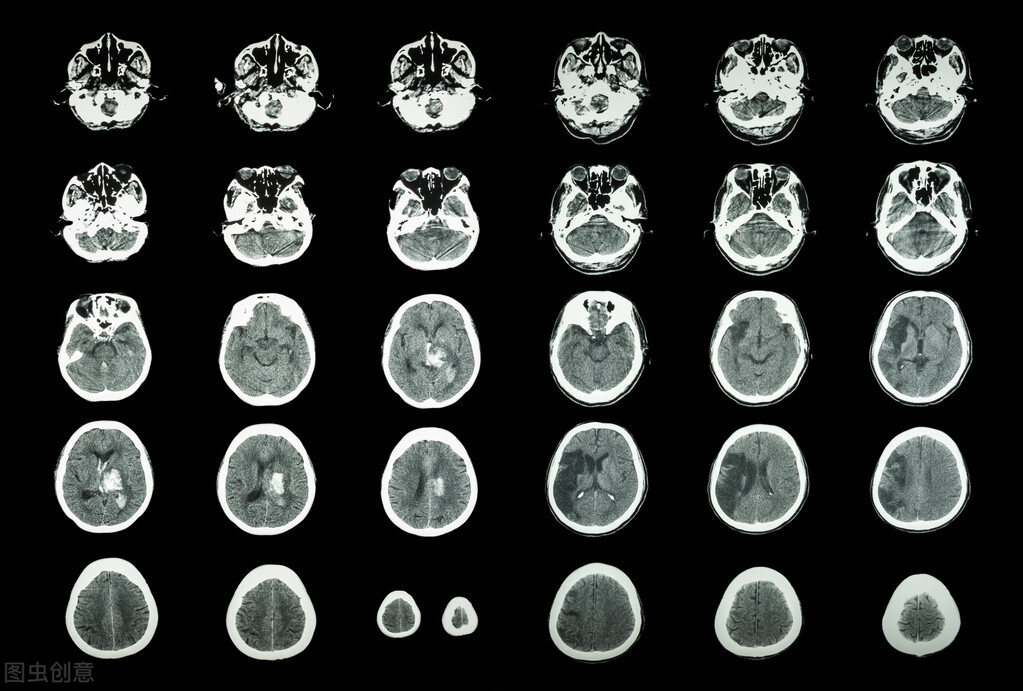

缺血性卒中患者急性期发作的治疗,除了恢复堵塞血管的再通外,更重要的是大脑侧支循环代偿,保护缺血半暗带残存的脑功能。急性期之后就是漫长的恢复期,缺血区的脑细胞一旦凋亡,即使血管再通之后也是不能再生的,因此,从这个角度出发,缺血性卒中一旦发作,没有任何药物能让凋亡的脑组织起死回生,那么,缺血性卒中患者服用一大堆药物,目的是什么呢?目的就是通过血压,血脂,血糖的管理,防止缺血性卒中的复发,降低脑梗死发作风险。因此,缺血性卒中的基本药物治疗,是一种综合措施,包括血压,血脂,血糖、抗栓治疗的管理,

缺血性卒中治疗的目的除了急性期恢复大血管再通外,闭塞动脉周围的小血管(侧枝循环)的代偿程度与预后密切相关,此外,神经保护剂的使用也能在一定程度上改善神经功能缺损的程度,因此,卒中出院后,对于肢体障碍的患者来说,肢体训练等康复治疗非常关键,药物治疗主要集中于改善侧支循环和神经保护剂的应用。相关指南提到的改善侧枝循环的药物主要包括丁苯酞,神经保护剂提到的仅有依达拉奉。